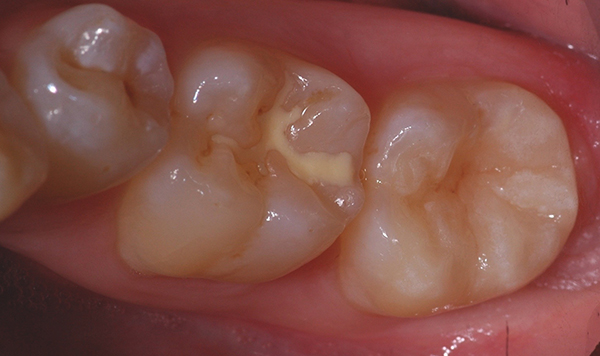

La messa in opera delle manovre odontoiatriche permette di raggiungere gli obiettivi sopraccitati ed esporre un contorno periferico di smalto che appariva sano e normale.

Alla luce di quest'aspetto ( smalto sano e normale periferico ) l'idea riabilitativa dell'elemento 4.7 è il confezionamento di un restauro parziale a ricopertura cuspidale in materiale ceramico e cementato con tecniche adesive ai tessuti dentali della cavità preparata.

Alla fine della procedura di preparazione dentale la cavità evidenzia ampie aree di dentina esposta ma altresì un contorno ben rappresentato di smalto sano e normale suscettibile al trattamento con procedure adesive smalto-dentinali.

La cavità si presenta abbastanza ampia e il restauro previsto dovrebbe ricostituire tutta la superficie masticatoria, le cuspidi di stampo vestibolari, la cresta inter prossimale distale e parte della cuspide disto-linguale.